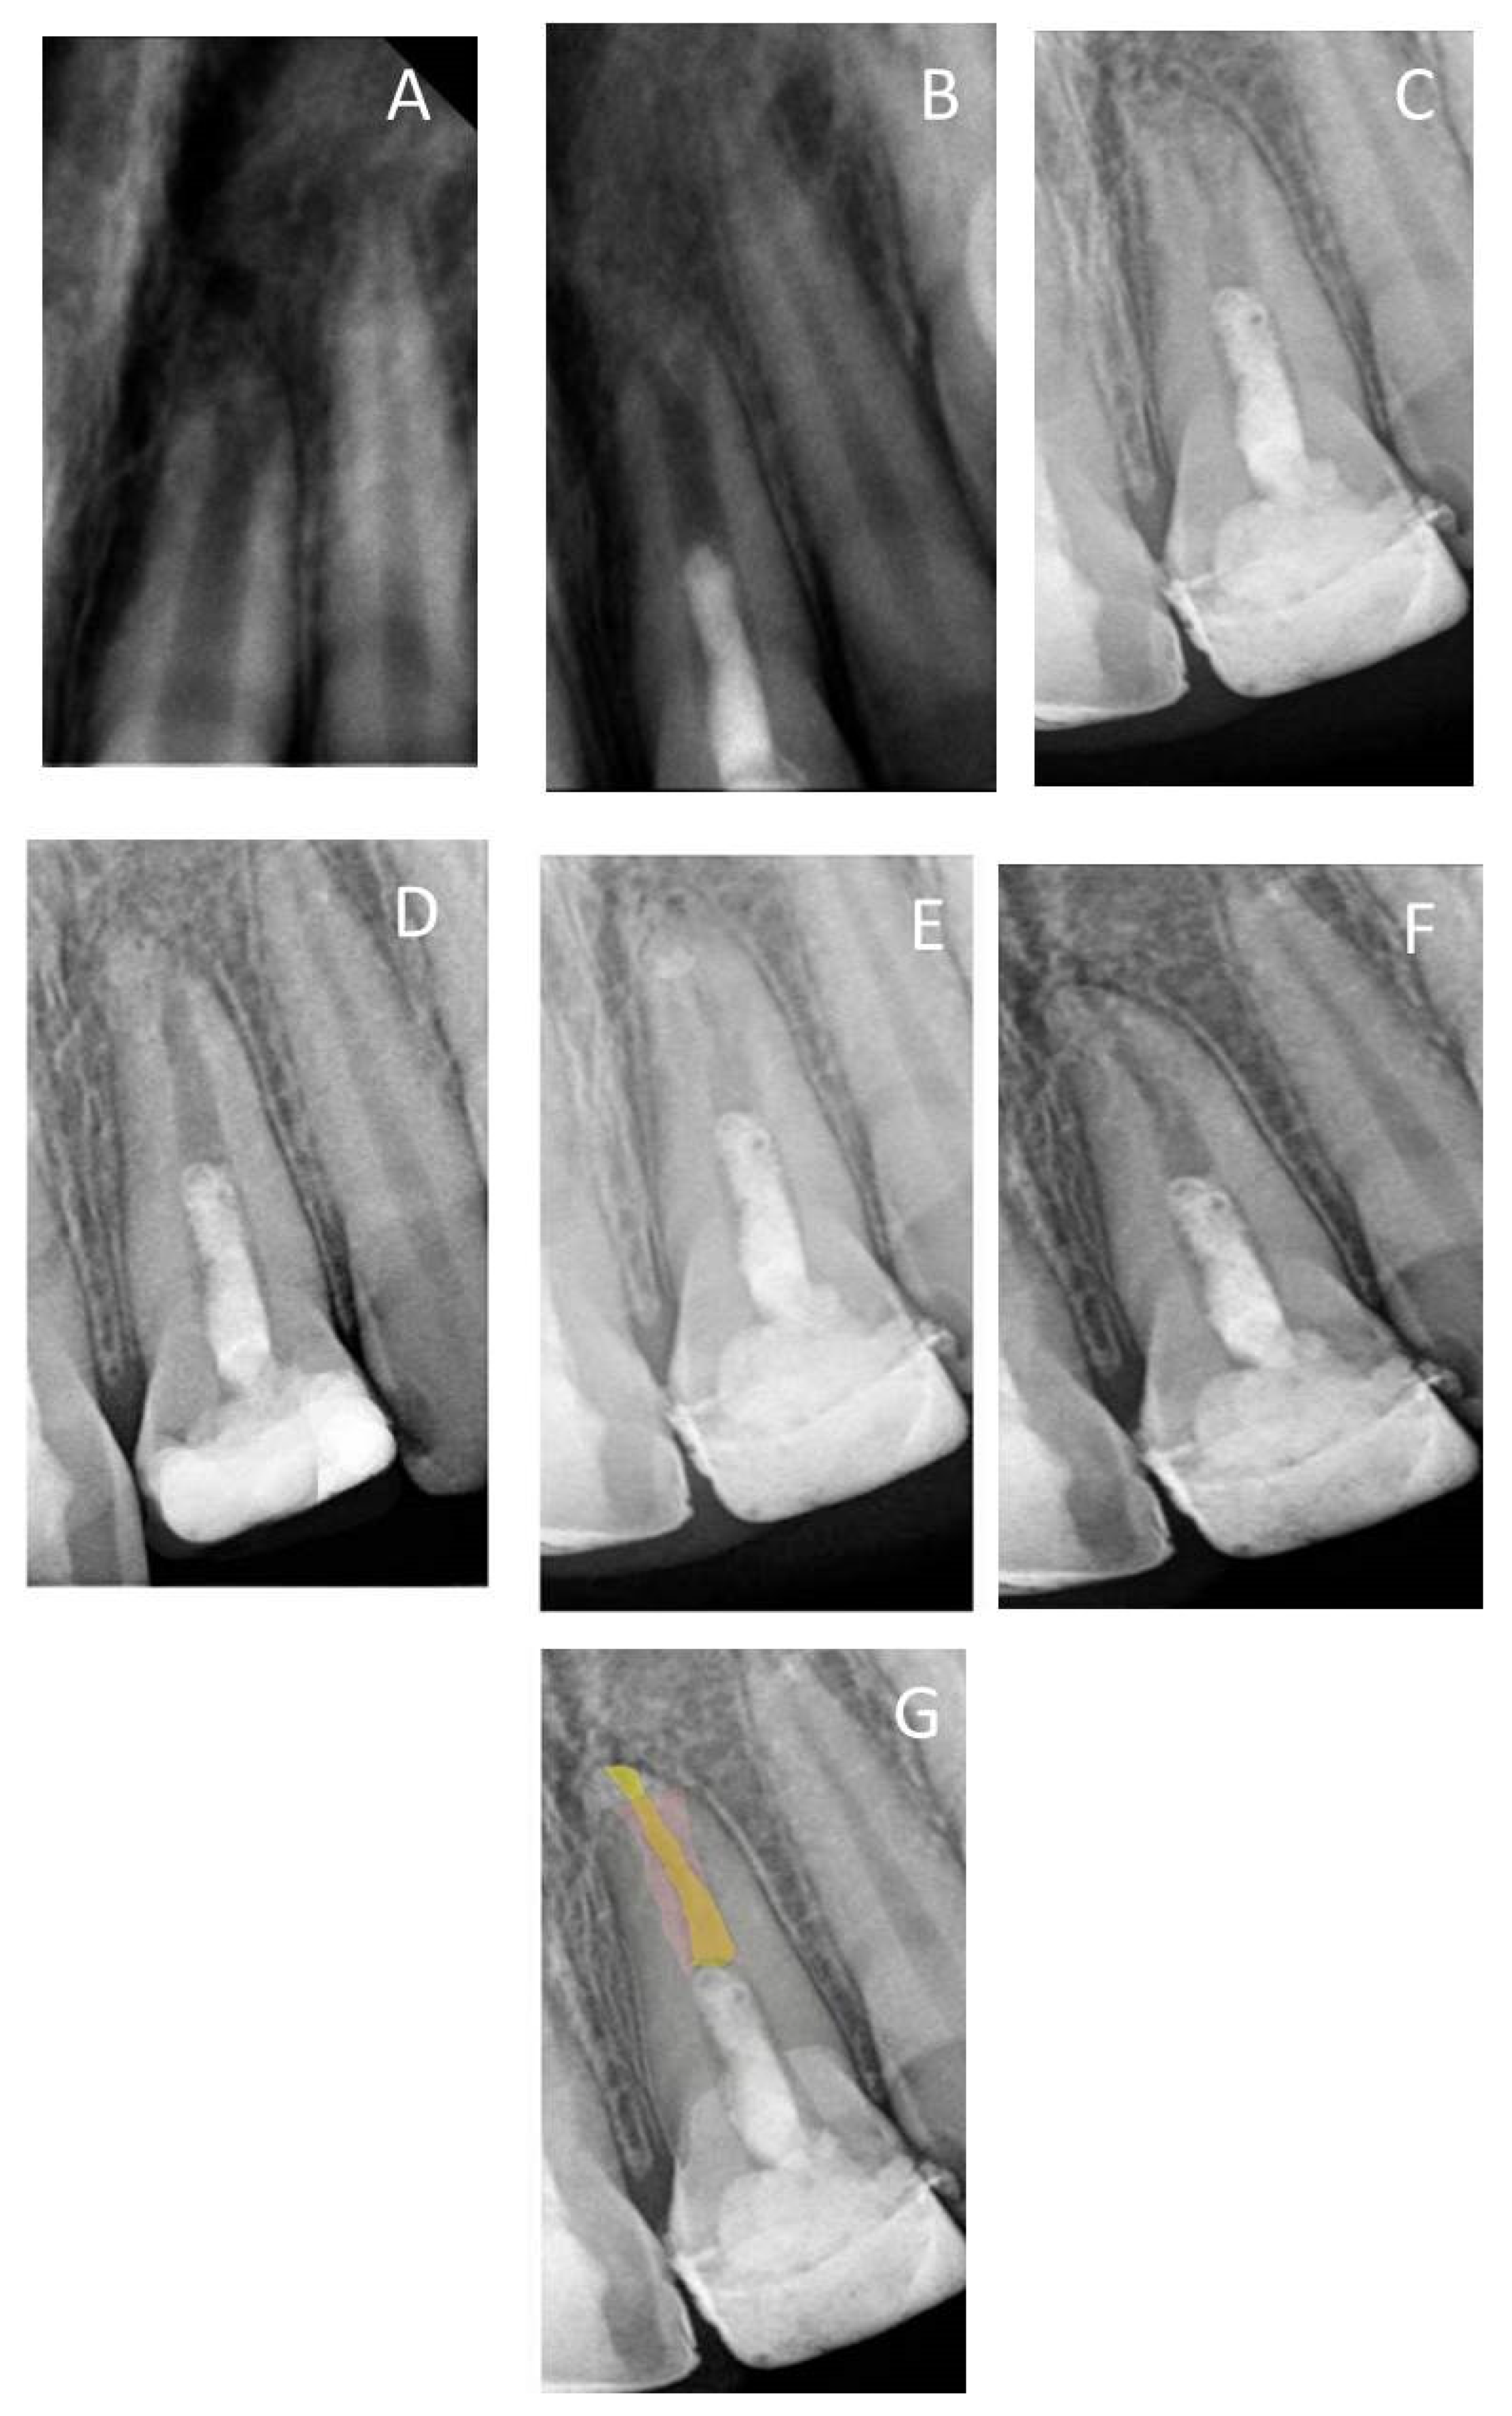

3. Results

3.1. Quantitative Assessment

3.2. Qualitative Assessment